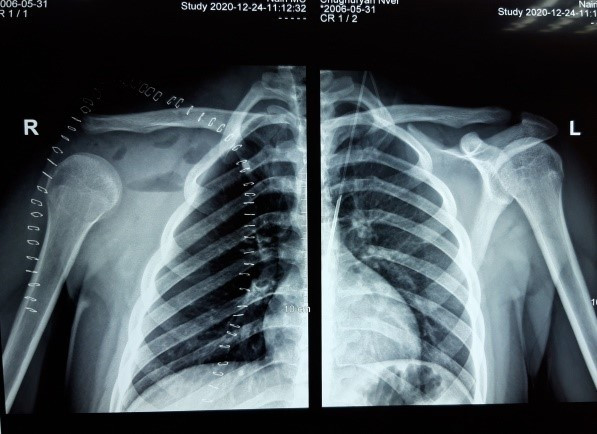

Рисунок 1. Радиологическое изображение лопатки

В представленном клиническом случае саркома Юинга лопатки была диагносцирована у мальчика 14 лет. Размеры образования изначально были большими и была поражена вся лопатка.

Серьёзной проблемой становится резекция плоских костей, играющих важную функциональную роль. К таким случаям относятся поражения лопаток. Лопатка, помимо важной функциональной нагрузки, имеет и эстетическую роль. Резекции тела лопатки, вне зависимости от их объёма, при сохранении гленоида не приводят к большим нарушениям функции. Однако при саркоме лопатки, когда ставится вопрос тотального удаления её, помимо функциональных нарушений, возникают вопросы эстетического ряда, связанные с провисанием верхней конечности. Это возникает в том случае, когда не удаётся сохранить акромиальный участок ключицы с её связками.